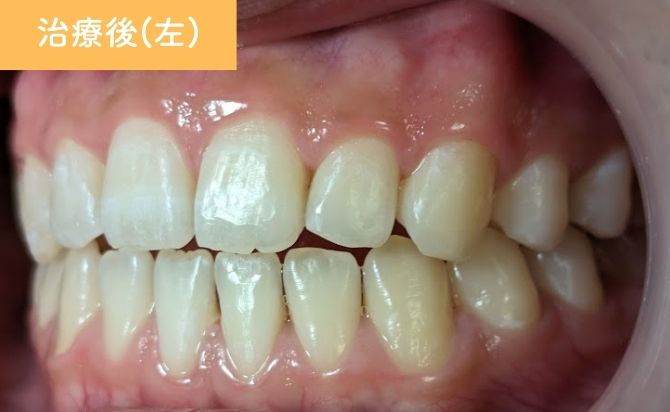

治療終了時には、上顎前歯の歯間空隙が閉鎖され、前歯部の開咬も改善しました。上下前歯の前突感が軽減され、歯列弓も自然な形態に整っています。

前歯部の見た目が大きく改善しただけでなく、噛み合わせも安定し、機能面・審美面の両立が図られた症例となりました。

現在は、後戻り防止のためリテーナー(保定装置)を使用していただき、経過観察を続けています。

歯並びの変化(左)